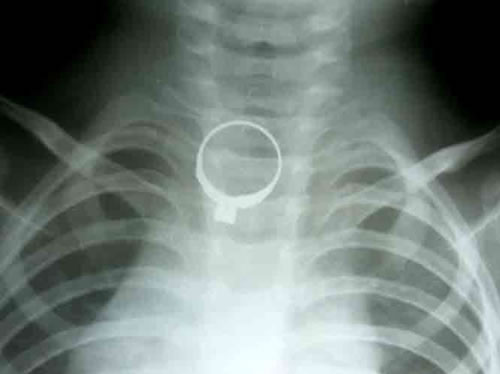

(Cadn.com.vn) - Chiều 5- 11, theo thông tin nhận được từ các bác sĩ Bệnh viện Hữu Nghị Việt Nam - Cu Ba Đồng Hới (Quảng Bình) bệnh viện vừa tiếp nhận bệnh nhi Trần Văn Minh (2012, trú xã Quảng Liên, H. Quảng Trạch, Quảng Bình), cấp cứu trong tình trạng nguy kịch. Trước đó cháu bé được người nhà đưa đến nhập viện với biểu hiện quấy khóc, đau tức vùng cổ. Mẹ của cháu cho biết trong lúc chơi đùa với mẹ, cháu đã đòi chiếc nhẫn của mẹ đeo trên tay. Chơi được một chút cháu liền ngậm vào miệng và nuốt xuống thực quản. Các bác sĩ đã chụp Xquang và phát hiện chiếc nhẫn nằm trong thực quản cháu bé, ngay sau đó đã tiến hành gắp chiếc nhẫn ra ngoài.